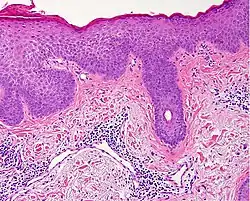

| Lichen planus | Irregular epidermal hyperplasia with a jagged “sawtooth” appearance, compact hyperkeratosis or orthokeratosis, foci of wedge-shaped hypergranulosis, basilar vacuolar degeneration, slight spongiosis in the spinous layer, and squamatization. The dermal papillae between the elongated rete ridges are frequently dome shaped. Necrotic keratinocytes can be observed in the basal layer of the epidermis and at the dermal-epidermal junction. Eosinophilic remnants of anucleate apoptotic basal cells may also be found in the dermis and are referred to as “colloid or civatte bodies”. Whickham striae are usually seen in the areas of hypergranulosis. Vacuolar degeneration at the basal layer may be noted leading to focal subepidermal clefts (Max Joseph spaces). Squamatization occurs as a result of maturation and flattening of cells in the basal layer. It happens in areas of marked hypergranulosis with prominence of the sawtooth pattern of rete ridges. Wedge-shaped hypergranulosis can occur in the eccrine ducts (acrosyringia) or hair follicles (acrotrichia). In the hypertrophic subtype, the associated hyperkeratosis, parakeratosis, hypergranulosis, papillomatosis, acanthosis, and hyperplasia markedly increased with thicker collagen bundles forming in the dermis. Moreover, the rete ridges are more elongated and rounded as opposed to the typical sawtooth pattern. In atrophic LP, loss of the rete ridges and dermal fibrosis is prominent. In vesiculobullous LP, the disease progression is quicker. Hence, some of the distinctive features such as hyperkeratosis, hypergranulosis, or dense lymphocytic dermal-epidermal infiltrate may not be present. LP lesion may resolve with residual hyperpigmentation caused by a persistent increase in the number of melanophages in the papillary dermis.[9] | ![]() |